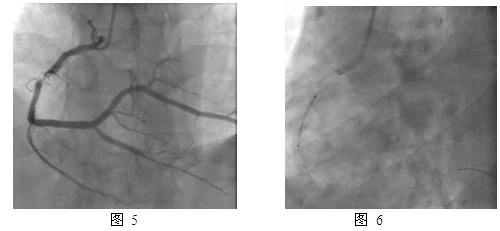

JR4.0指引导管,BMW导丝,预扩张球囊Fire Star 2.5mm x 15mm,最大20atm扩张;双导丝球囊Score Flex 3.5mm x 15mm,最大16atm扩张(图2);后扩张球囊Sapphire NC 3.75mm x 15mm,最大10atm;紫杉醇药物洗脱球囊(PEB)Sequent please 3.5mm x 20mm,最大18atm扩张,持续60s(图 3)。最终效果满意(图 4)。

一年后,2013年2月患者再次出现活动时胸痛,特别是在高原地区。第三次住我院,复查冠脉造影:右冠支架内PEB治疗部位再狭窄80%(图5)。本次介入治疗于右冠支架内狭窄部位经球囊预扩张后置入XienceV支架 3.5mm x 23mm, 最大16atm扩张(图6),并用后扩张球囊Quantum 3.5mm x 15mm, 最大24atm 扩张,最终效果满意(图7)。